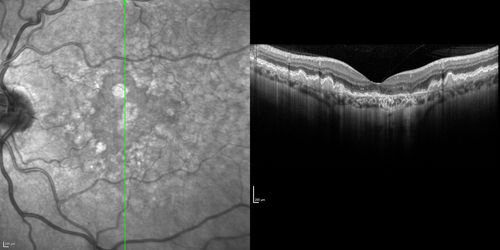

Dry AMD - Confluent Drusen Sparing Center of Macula which has Atrophy

65 year old woman, VA 20/40 OD; 20/80 OS. The center of the macula has few or no drusen with predominantly non-geographic atrophy